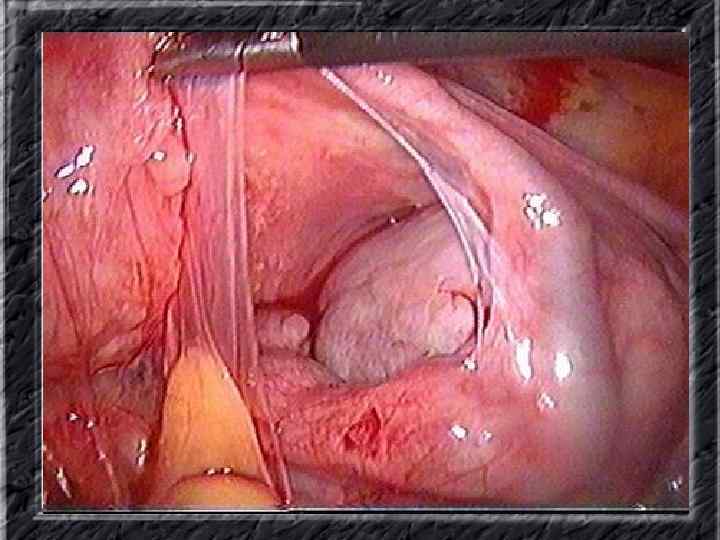

Названия слайдов: • • • Слайд 51. Ультрасонография: интерстициальный и истмический отделы маточной трубы. Слайд 52. Лапароскопия: неизмененная правая маточная труба. Слайд 53. Ультрасонография: многокамерная форма сальпингита. Слайд 54. Лапароскопия: относительно равномерное утолщение маточной трубы при гидросальпинксе. Слайд 55. Лапароскопия: вид маточной трубы при гидросальпинксе. Слайд 56. Гистеросальпингография: неравномерное расширение и деформация маточных труб. Слайд 57. Прервавшаяся трубная беременность: плод; макропрепарат. Слайд 58. Гематосальпингс, развившийся вследствие внутреннего разрыва плодо-вместилища при трубной беременности; макропрепарат. Слайд 59. Лапароскопия: значительное увеличение участка маточной трубы при трубной беременности. Слайд 60. Лапароскопия: скопление крови в полости малого таза в результате трубного аборта.